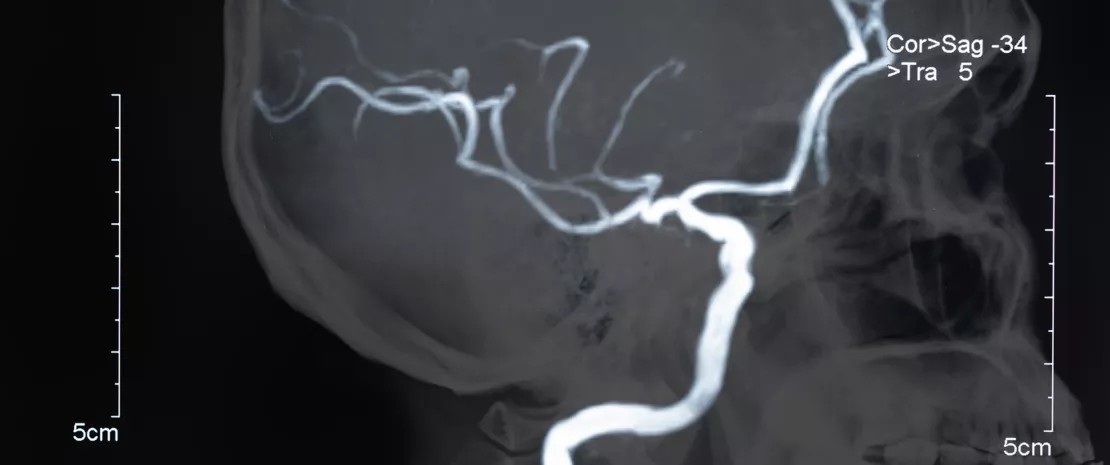

Con cerca de 25 millones de casos al año, el ictus isquémico agudo representa un desafío importante para la salud pública a escala mundial. Hasta el momento, el pronóstico es difícil de establecer y podría beneficiarse de la identificación de factores de riesgo de evolución adversa. Este hallazgo llevó a un equipo de investigación chino a desarrollar el Stroke Dysbiosis Index (SDI), un índice que relaciona el ictus y la disbiosis intestinal y cuyo objetivo es confirmar el accidente cerebrovascular y determinar la severidad de las lesiones cerebrales, así como el riesgo de complicaciones tempranas.